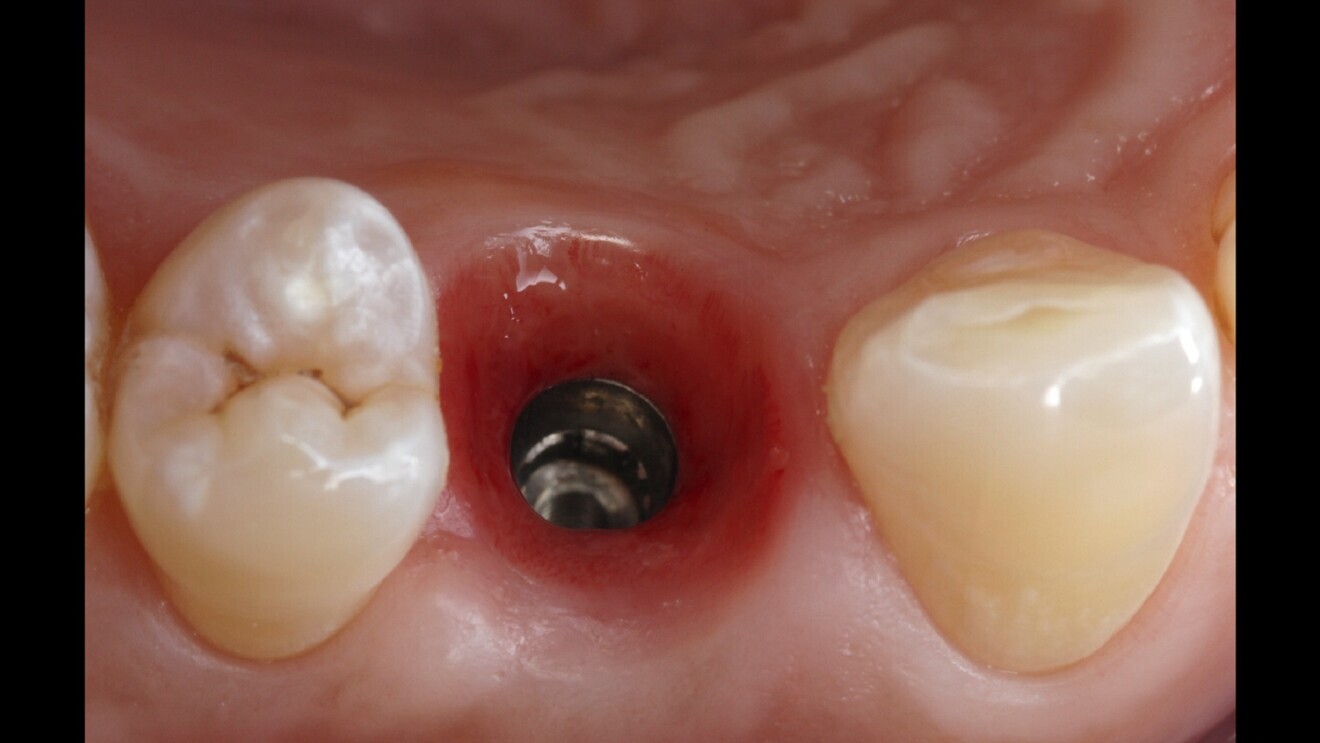

Fig. 7: Extracted tooth #14.

A 42-year-old male patient required extraction of his maxillary right first premolar (tooth #14; Fig. 6). The patient’s high smile line and need for immediate rehabilitation posed challenges. Atraumatic extraction preserved the tissue and bone profile (Fig. 7).